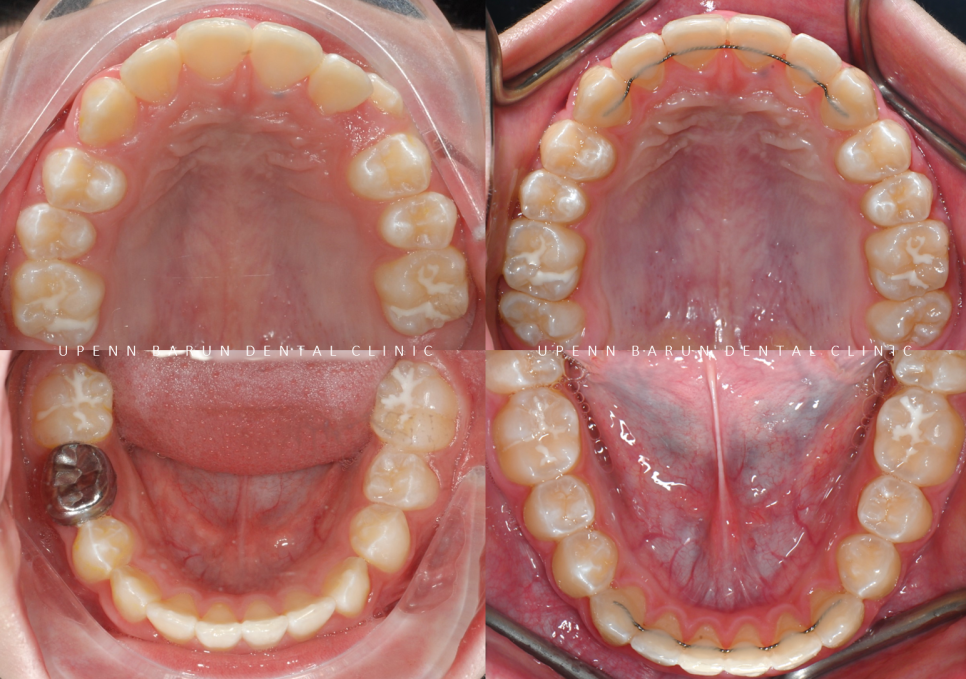

4th(14개)

마지막으로 섬세한 디테일링을 위해

네번째 클린체크

(총 14개의 장치)를 진행해드렸습니다.

이전의 클린체크와는 어태치먼트의 모양과 위치가

달라져

이전의 클린체크를 보완해 교정치료의 완성도를 높여 줍니다.

마지막 클린체크를 통해

마무리된 치아배열을 확인해 보실까요?